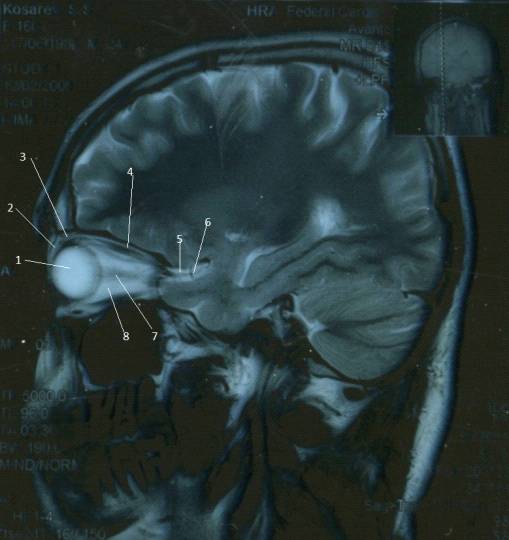

КТ-графики и изображение строения глаза